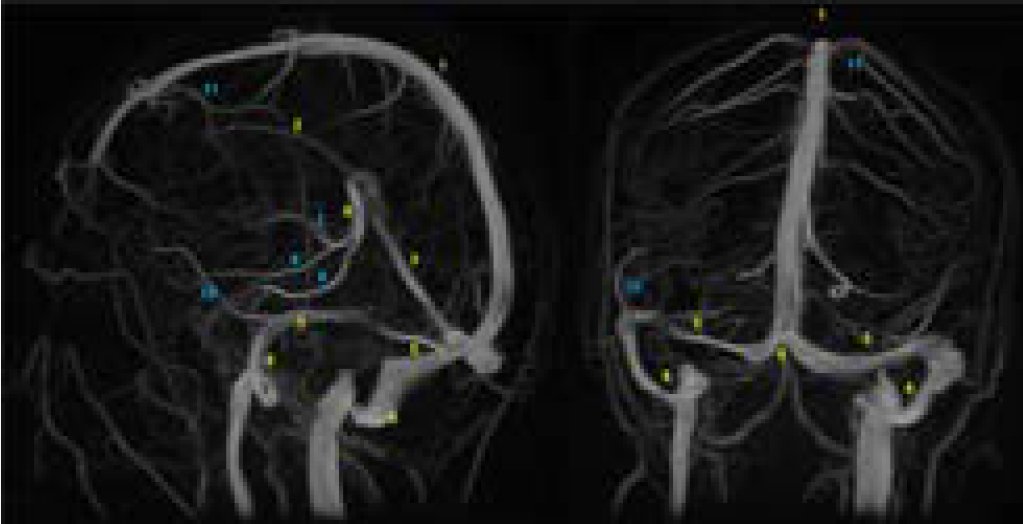

Azygos Anterior Cerebral Artery (~0.3-2% prevalence) – A single vessel replaces the paired ACAs, centralizing blood supply This makes it vulnerable to complete anterior territory infarction, possibly presenting as sudden bilateral lower extremity weakness

Azygos Anterior Cerebral Artery (~0.3-2% prevalence) – A single vessel replaces the paired ACAs, centralizing blood supply

This makes it vulnerable to complete anterior territory infarction, possibly presenting as sudden bilateral lower extremity weakness